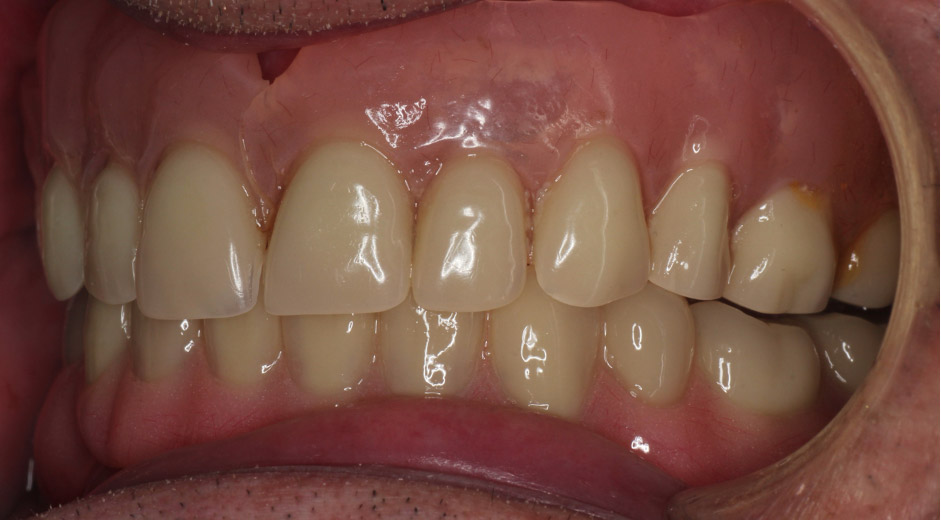

- Complete dentures

- Conventionally it is thought that bilateral balanced occlusion benefited complete dentures. However, this is not shown in the literature (Abduo, Tennant and McGeachie, 2013; Lemos et al, 2018; Zhao et al, 2013). Bilateral posterior balanced contacts in maximal contact position are far more important for denture occlusion (see Figure 4).